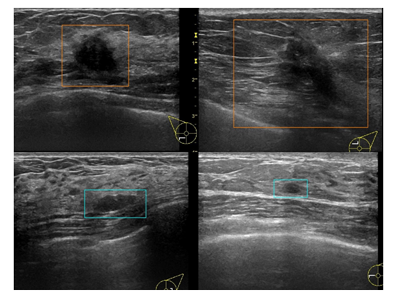

画像はリリースより

実現するために、コンピュータの性能を最大限に引き出す高速化技術を社会に提供している株式会社フィックスターズが開発したConvolutional Neural Network(CNN)をベースとしたディープラーニング技術を利用し、初めに慶應義塾大学が提供する約1,500枚のアノテーション済み乳房超音波画像を教師データとして学習させたAI診断システムの構築を行った。その結果、AIが高い精度で検査画像中の腫瘍を認識して、良悪性の判定を一枚あたり0.01秒以下で行うことが可能だった。

このAIを臨床応用するために、さらなる精度向上を目指して、同大を含む共同研究施設から7,194枚の乳房超音波画像を収集し、その全てにアノテーション作業を行った。これを教師データ(4,028枚)とテストデータ(3,166枚)に二分し、AIシステムの構築と検証に使用した。

これらの背景から、研究グループはAIの臨床応用を目指すにあたり、良悪性の判断を行うのではなく、乳房超音波検査画像に含まれる病変が、このBI-RADS基準において乳がんの頻度が高まる BI-RADSカテゴリー4以上なのか、乳がんの可能性がほとんどないBI-RADSカテゴリー3以下なのかを判定するAI診断システムを構築した。

AI診断システムの精度は感度91.2%、特異度90.7%

このAIを用いて、前述の教師データとは異なるテストデータ(3,166枚の乳房超音波静止画像)を対象として診断を行ったところ、感度91.2%、特異度90.7%の精度で診断が可能であることが明らかになった。判定の閾値を変化させて描いたROC曲線におけるAUCの値は1に近づくほど診断システムの精度がよいことを表すが、このAI診断システムのAUCは0.95であり、非常に精度が高いことが示された。

加えて、このAI診断システムと10人の外科専門医を含む計20人の臨床医による、30枚の乳房超音波検査画像に対する診断精度比較を行ったところ、感度・特異度ともに統計学的に有意な差をもってAIが優れた精度での診断を行うことができた。